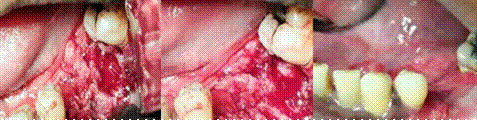

Figura 3.

Se observa al esión esión intraoral esión ulcerosa, eritematosa rodeada de lesiones exofiticas queratinizantes color blanquecino de consistencia indurada sospechosa de malignidad. B: Toma de muestra, biopsia excisional realizada por la Dra. Beatriz Acosta, jefa de servicio de odontología Cpt3 Gran Sabana y autores de esta investigación. Fecha 17/06/24. C: Excision total de la lesión con extensiones a bordes sanos.

3ª                               3b                           3c

A nivel extraoral se observa inflamación en el lado postero inferior izquierdo a nivel del cuerpo de la mandíbula. (Figura 2). Al realizar la extracción se observa en la región del reborde alveolar postero inferior una lesión ulcerosa, eritematosa de aproximadamente 2,5 cm, lesiones exofiticas indoloras color blanquecino, de consistencia dura de aproximadamente 3cm. (Figura 3). Se procedió a la toma de muestra o biopsia excisional para la posterior remisión al anatomo patólogo y el debido estudio histopatológico.

(Figura 3b y 3c).